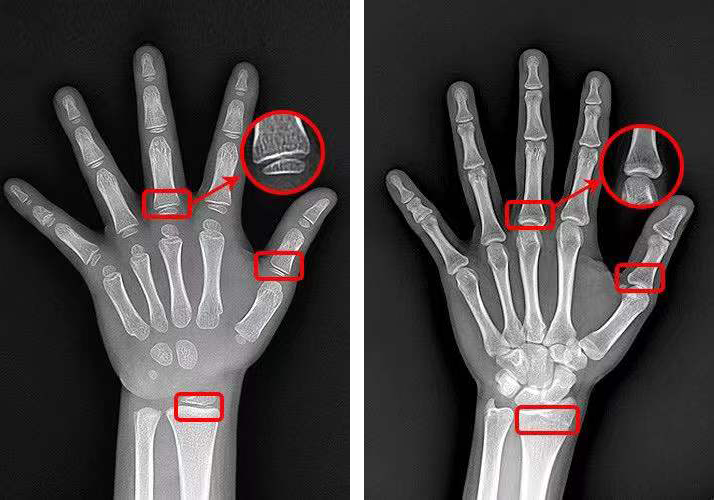

案 例 16岁的男孩小杨身高才156厘米,而且父母发现小杨今年身高没什么变化,好像已经停止生长了,赶紧带着他来看医生。 经过骨龄检查,结果显示小杨骨龄已经18岁了,比实际年龄早了2岁,再也没有长高的机会。即便注射生长激素进行干预,但根据骨龄预测小杨的成年终身高很有可能达不到1米6,因为他已经错过最佳的生长干预期。诊断结果让小杨父母追悔莫及。 ▲小杨的骨干骺端接近闭合 骨龄,决定着生长空间 骨龄就像车上的汽油,用一点少一点。 骨龄跑的慢,油耗低,跑得远跑的长; 骨龄跑得快,油耗高,跑得近跑得短。 我们看下还有生长空间的孩子生长板是什么样的: ▲左图为4.7岁孩子的生长板,清晰可见 右图为17岁男孩,骨干骺端完全闭合,生长板消失 ▲膝关节X光片 通过小杨的案例, 我们可以得到下面两个重要结论: 一、定期监测骨龄,评估生长发育情况 为什么医生总是提醒家长,孩子应该从3岁开始定期监测骨龄? 定期监测骨龄,能够及时地评估孩子的生长发育情况,预测孩子还能长多高,成年终身高是多少,医生也可以因此制定相应的身高管理方案,帮助孩子达到理想身高。 骨龄检测(3-15岁), 预测成年终身高、判断发展潜力 售价258元, 点击下图即可了解详情~ 点击↓↓↓ 二、生长期要抓牢,身高管理要尽早 一个人身高的80%是在青春期之前完成的,越小进行身高管理,骨干骺端距离闭合的时间越长,干预的方法也越多。每早一年干预,孩子就可能多长1-2cm,越容易达到期望身高。 越晚进行身高管理,不仅干预的方法少,花费也更高,达到期望身高的难度也更大。 科学长高管理(3-14岁), 定制管理计划,特色管理方案, 仅需1280元/年! 点击下图即可了解详情~ 点击↓↓↓ 最后,提醒各位家长朋友,如果孩子的身高一直不理想或者想要孩子长到期望身高,就应该尽早地做身高检查,评估生长发育情况,尽早干预,做好身高管理,定期监测骨龄。